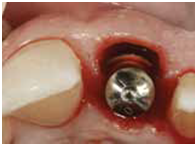

98/01/08經過三個半月做右下第一小臼齒的二階暴露,發覺鄰牙的植體高度竟已掉下來

980305幫患者補角化牙齦並翻開清除發炎組織,期待能阻止繼續骨破壞